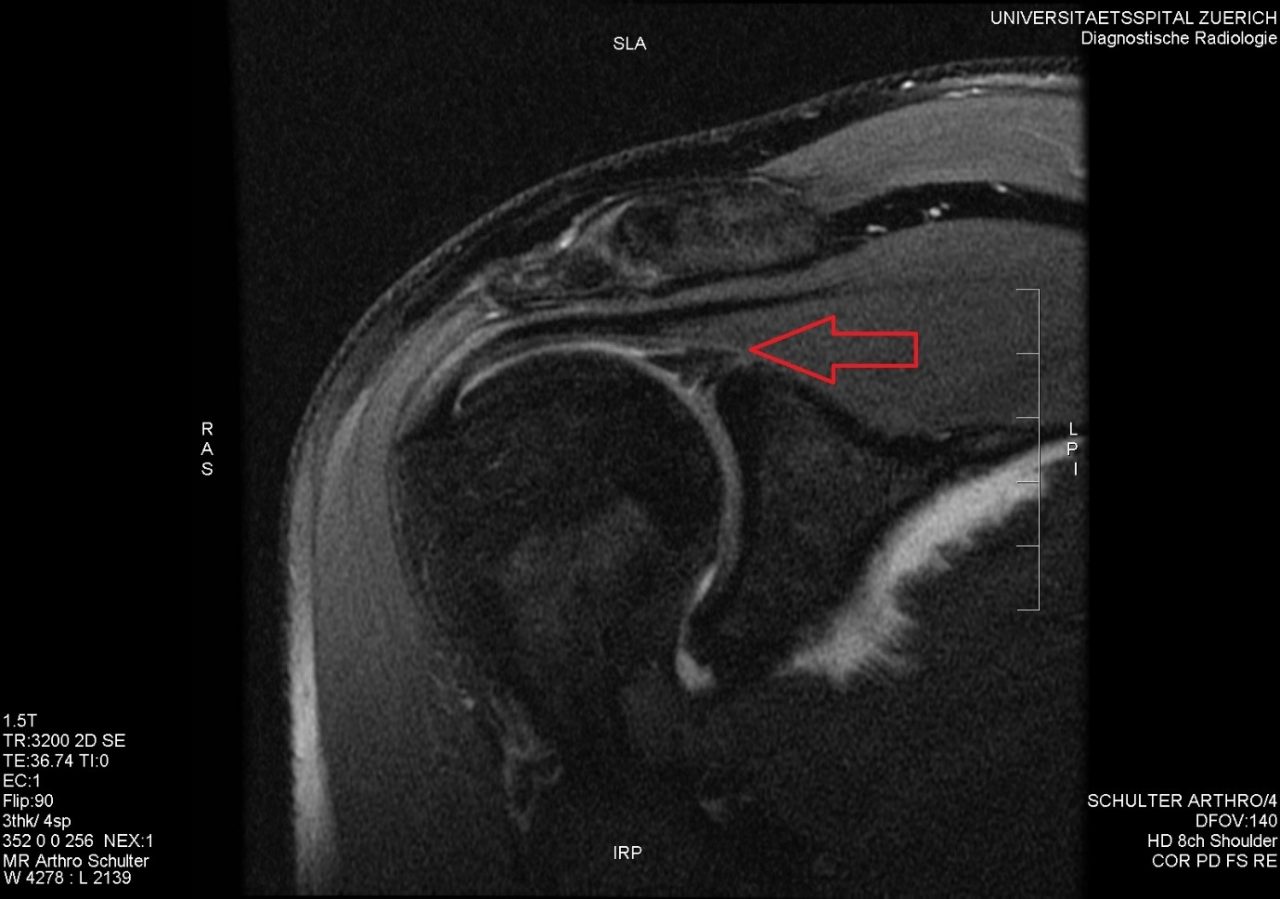

From www.semanticscholar.org

Figure 1 from MR Arthrography Superior Labral AnteriorPosterior Throwing Labral Tear learn about the anatomy, causes, symptoms, diagnosis, and treatment of a labral tear, a common shoulder injury that can affect stability and. slap stands for “superior labral anterior to posterior tear”, meaning a tear of the upper rim of the labrum, from front to back. Typical symptoms of a slap tear include a catching sensation and pain with. Throwing Labral Tear.

From www.pinterest.ca

Mri Arthrogram, Glenoid Labral Tear Medical imaging, Radiology, Mri Throwing Labral Tear Find out when surgery is. a slap tear is an injury to the labrum of the shoulder, a ring of cartilage that deepens the socket and stabilizes the joint. learn about the anatomy, causes, symptoms, diagnosis, and treatment of a labral tear, a common shoulder injury that can affect stability and. The glenoid labrum is most. It can. Throwing Labral Tear.